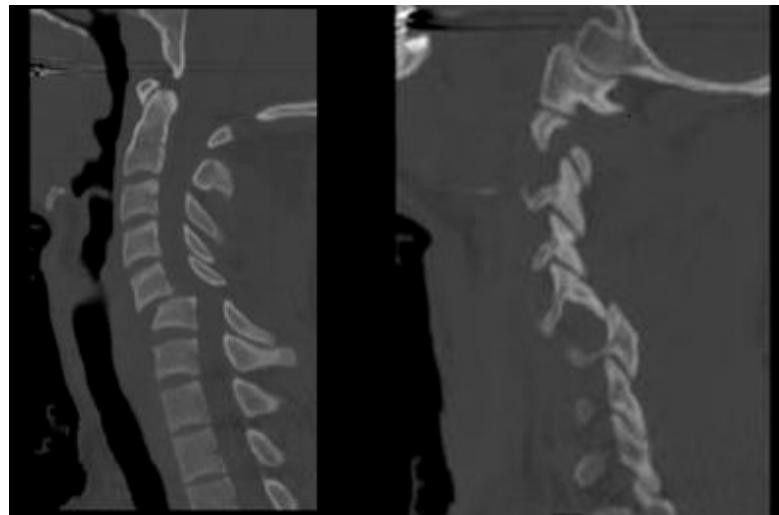

- Diagnosis: Standard lateral and open-mouth odontoid radiographs; CT scan for difficult cases

- Gold standard investigation: CT scan